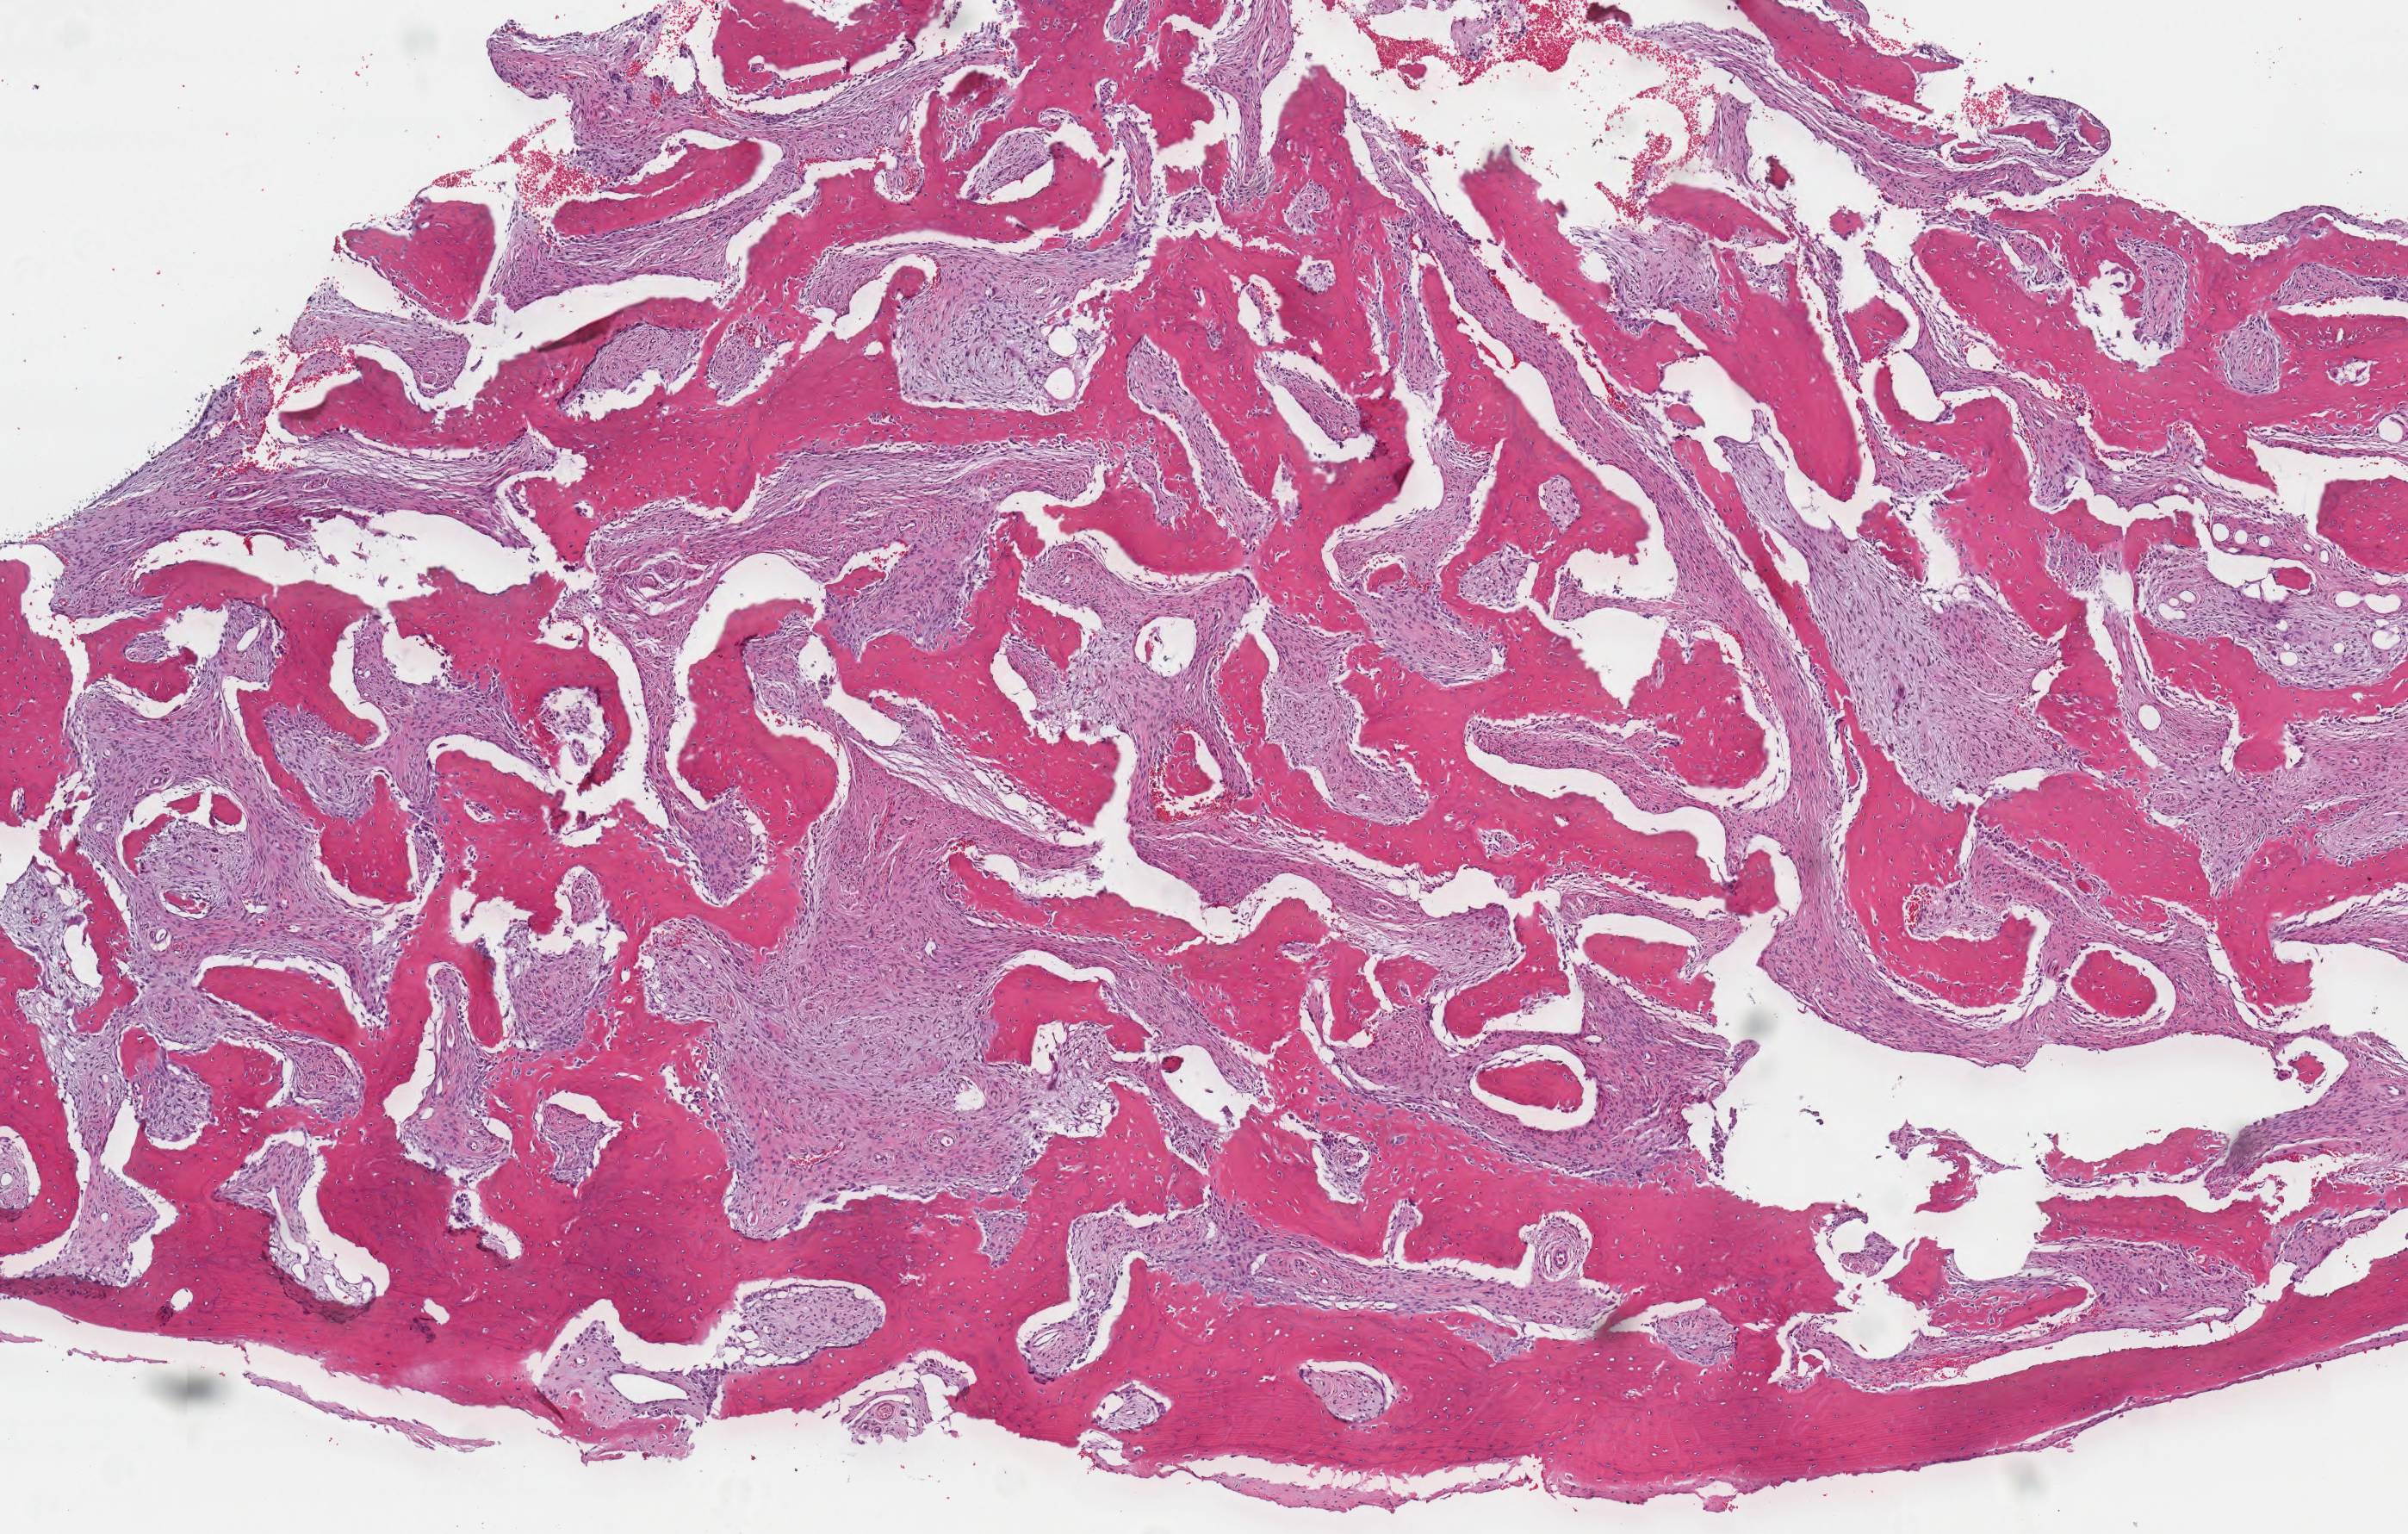

Microscopic (histologic) description

- Branching and anastomosing irregular trabeculae of woven bone ("C" and "S" shapes) with no conspicuous osteoblastic rimming

- No / rare osteoclasts

- Intervening fibrous stroma containing cytologically bland spindle cells, without prominent cytologic atypia

- Mitotic figures rare

- Stromal changes, including myxoid change and fatty metaplasia, may be seen in some cases (BMC Musculoskelet Disord 2003;4:20)

- Secondary aneurysmal bone cyst-like changes may also be seen (Turk Patoloji Derg 2018;34:234)

- Fibrocartilaginous dysplasia: uncommon variant containing variable proportions of cartilaginous differentiation and enchondral ossification (Am J Surg Pathol 1993;17:924)

- Growing collagen (Sharpey's fibers) may form perpendicular to the sites of bone formation but are not essential for diagnosis (Oral Dis 2017;23:697)

Microscopic (histologic) images